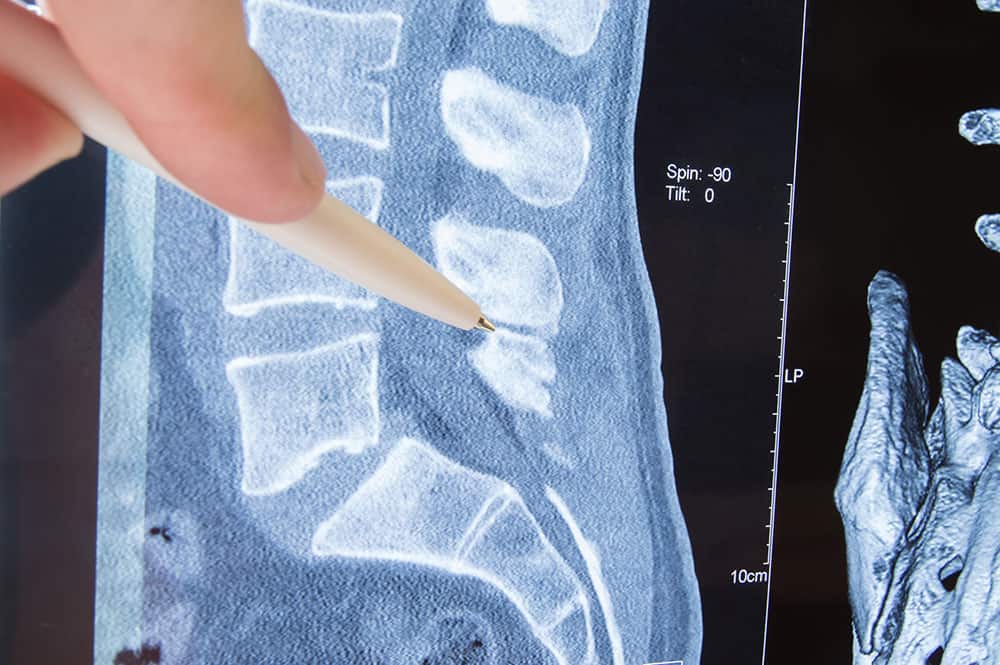

Canal Stenosis is caused by narrowing along the spinal canal which contains the spinal cord. It is the same condition as spinal stenosis.

Acquired stenosis, the second type, is more common and develops through the long-term processes of degeneration of the three-joint complex that consists of the intervertebral disc, the inferior and superior vertebral bodies and the facet joints. With the third decade of development, synovitis, or inflammation of the synovial joints in the spine, can occur. Osteophytes can form narrowing the foramina, root canals and spinal canal. Herniated and slipped discs can also participate in the biomechanical degeneration that also loosens the facet joints, increases spine instability and leads to spinal stenosis(1). The process gets worse. The narrowing not only places pressure on the neural system, but it also impinges the vascular system which results in ischemic neuritis which adds to the symptoms.